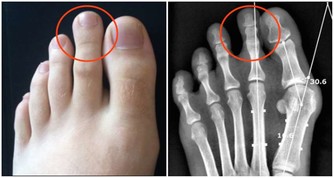

引起手麻較為常見原因的有以下幾種: 上肢神經卡壓:

一是拇、食、中指的麻木疼痛,

常有夜間麻醒史,醒後活動可好轉。

嚴重者可伴有手部肌肉萎 縮,影響手的精細動作,

這是因為正中神經在腕部受到壓迫,

即所謂的「腕管綜合徵」;

二是環、小指的麻木疼痛,也可有夜間麻醒史,

嚴重者伴有肌萎縮,環、小 指的屈指力下降,

影響精細動作。這是因為神經在肘部受到卡壓,

即所謂的「肘管綜合徵」。

確診頸椎病並不困難,只要照一張X光片就可以了。